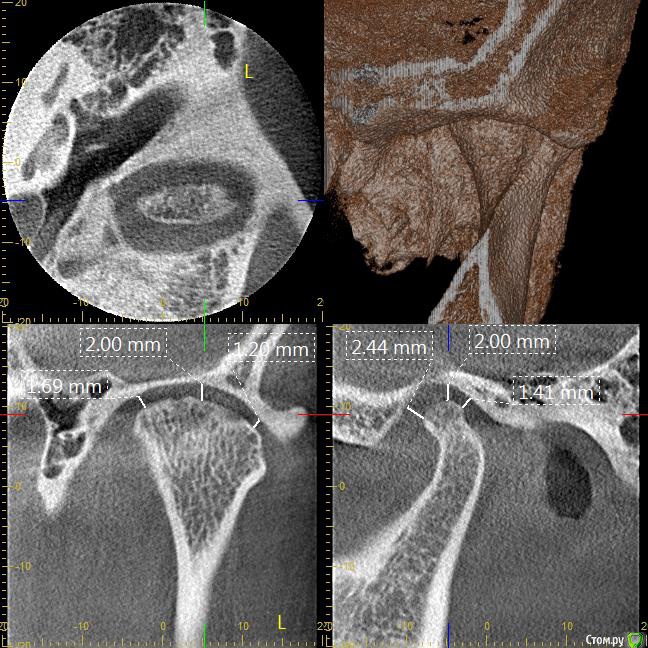

Мне 31 год. В детстве мне выбили верхний зуб 2-ку. Собираюсь лечиться брекетами, а потом вставлять имплант на место двойки. Но у меня есть еще проблеми с ВНЧС (с детства болит, хруст, щелчки), делала недавно КТ ВНЧС, диагноз артрит или артроз. Ходила к многим специалистам, все говорят разное. Надо ли проводить лечения капой моей дисфункции ВНЧС до установки брекетов или после установки брекетов?